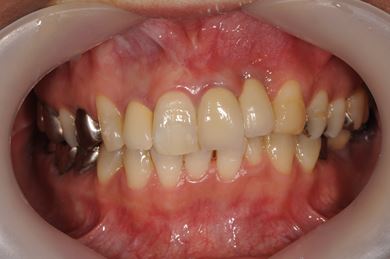

骨再生インプラント治療+セラミック治療

| カテゴリー | 【インプラント治療】【セラミック治療】 | ||||||||||||||||||||||||||||||||

| 性別/年齢 | 女性 / 48歳 | ||||||||||||||||||||||||||||||||

| 主訴 | 他の歯科で、前歯の差し歯が折れたところにインプラントをすすめられているので、費用や期間など知りたい。 | ||||||||||||||||||||||||||||||||

| 治療方針 | 骨再生法により、インプラント治療を可能にする。 | ||||||||||||||||||||||||||||||||

| 治療内容 | インプラント1本、メタルボンドセラミッククラウン2本、GBR | ||||||||||||||||||||||||||||||||

| 総治療費 | 618,660円 | ||||||||||||||||||||||||||||||||

| 治療期間 | 9ヶ月 |